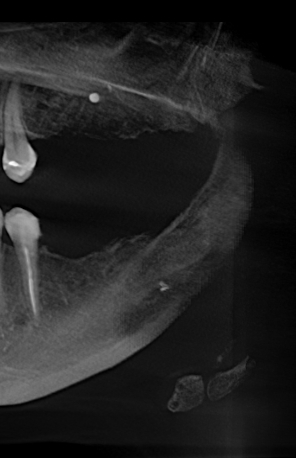

Может ли быть, что через пять лет мне аукнулся неудалённый материал, и боли будут только усугубляться? Прилагаю скриншот КТ

Теоретически ваши симптомы могут быть связаны с инородным материалом в надкостнице, но я не думаю, что причина ваших беспокойств связана именно с этим материалом. Необходимо хорошенько изучить область беспокойства.